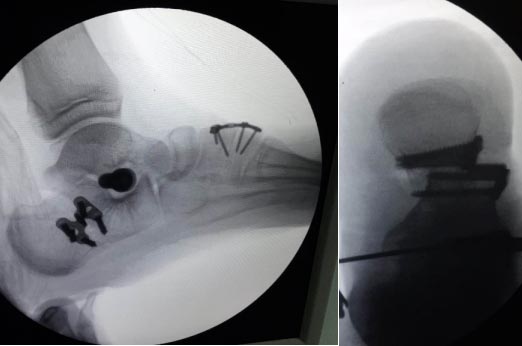

根據(jù)病情,小兒骨科積極邀請(qǐng)昆明醫(yī)科大學(xué)第二附屬醫(yī)院骨科足踝專家進(jìn)行會(huì)診及手術(shù)指導(dǎo)。經(jīng)我院小兒骨科和昆明醫(yī)科大學(xué)第二附屬醫(yī)院骨科足踝專家的配合,對(duì)該復(fù)雜僵硬性扁平足患者進(jìn)行了左側(cè)扁平足跟骨內(nèi)移截骨鋼板固定,距下關(guān)節(jié)制動(dòng)器置入,副舟骨切除,脛后肌腱止點(diǎn)重建術(shù),腓長(zhǎng)肌松解,內(nèi)側(cè)楔骨截骨植骨鋼板固定,取同側(cè)髂骨植骨術(shù)等多處復(fù)雜性手術(shù)治療,手術(shù)歷經(jīng)2小時(shí),圓滿順利完成。

上圖為患者扁平足術(shù)中影像資料